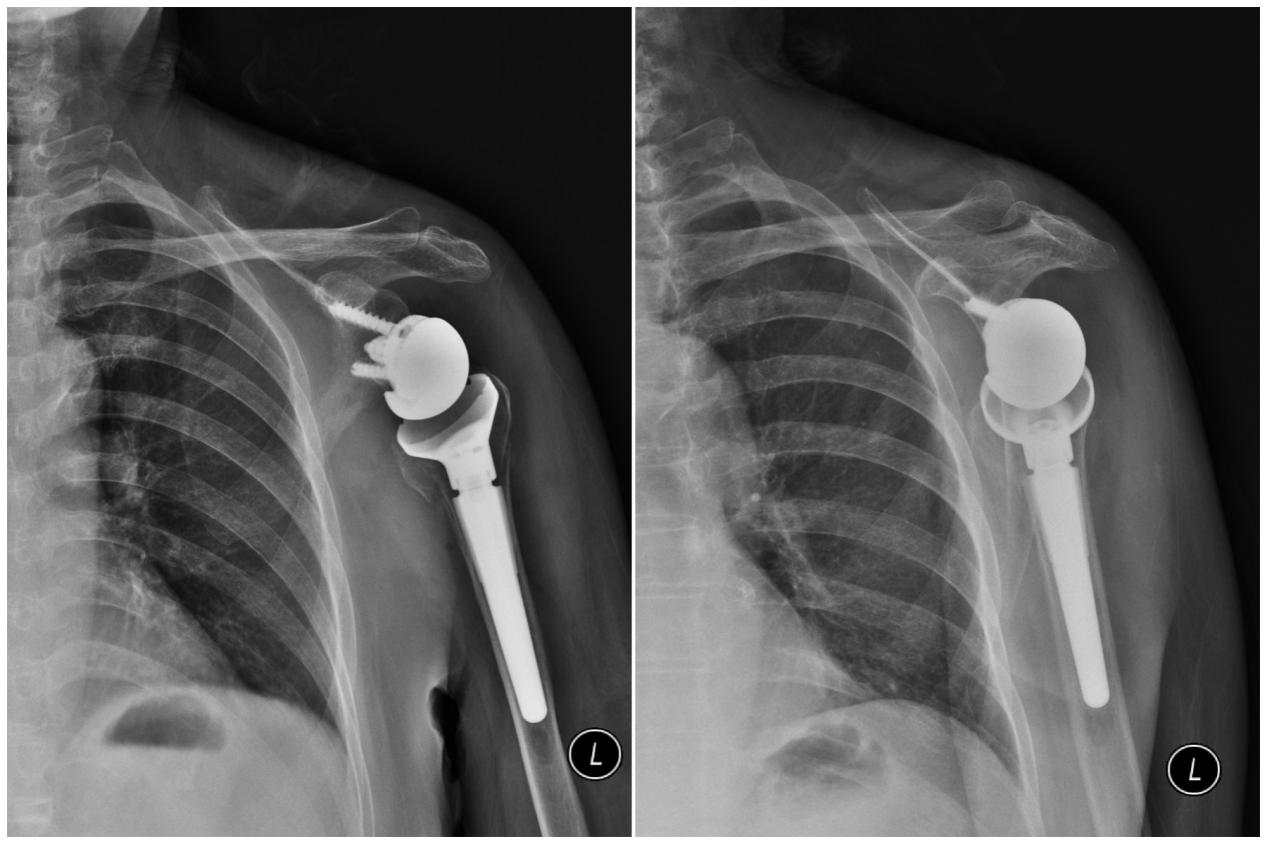

2月8日上午,在麻醉科、第一手术区医护团队的全力支持下,徐执扬、吴冯胜会同创伤骨科(骨一科)主治医师梁喜斌,共同为患者实施了人工反式全肩关节置换术。手术过程十分顺利。术后,患者恢复良好,并在医护团队的帮助下积极配合康复训练。术后一周,患侧肩关节已能外展活动接近90度,并于2025年2月13日出院。

▲人工反式全肩关节置换后